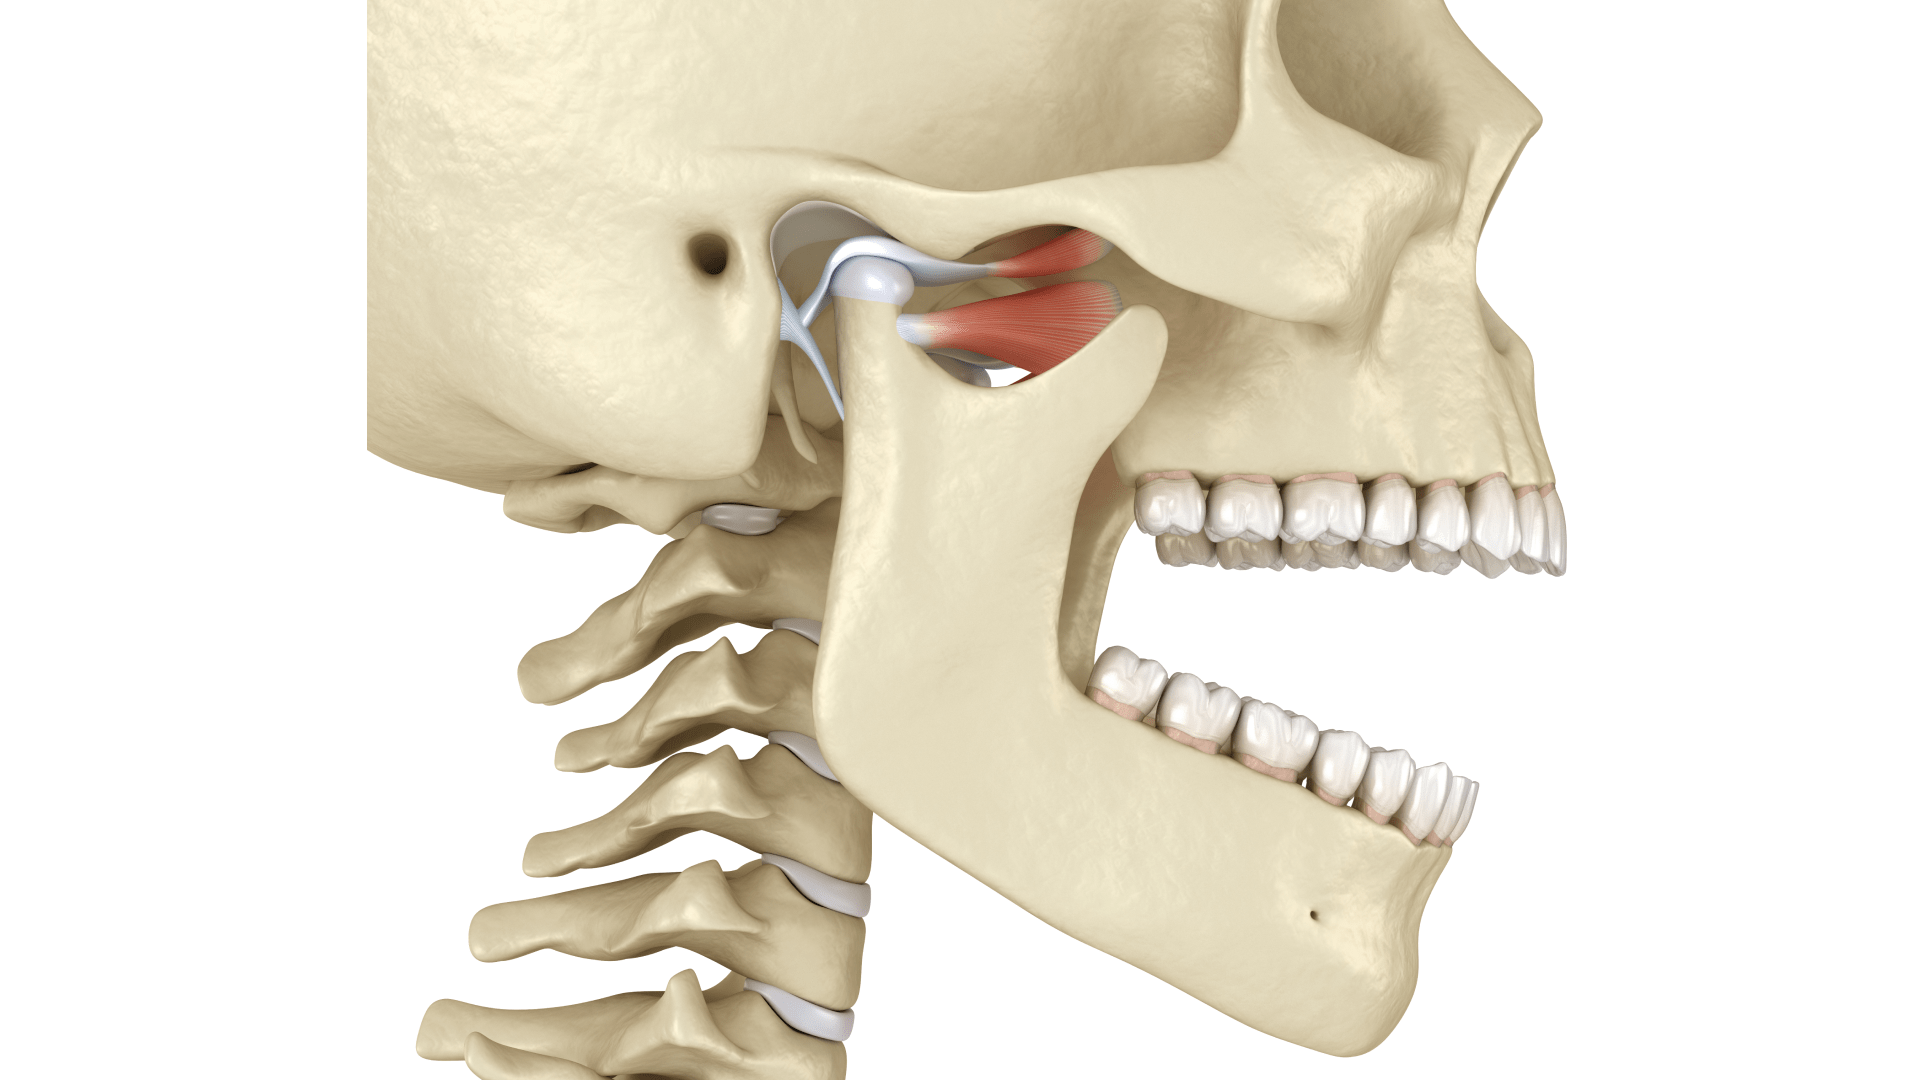

Скронево-нижньощелепний суглоб (СНЩС) — це парний суглоб, що з’єднує нижню щелепу зі скроневою кісткою черепа. Він є одним із найскладніших в організмі людини, адже може виконувати широкий діапазон рухів — відкривання, висування, обертання та зміщення щелепи вбік. Завдяки цьому ми можемо жувати, говорити, ковтати й навіть виражати емоції через міміку.

СНЩС має складну анатомію. Він складається з:

- суглобової головки нижньої щелепи;

- суглобової ямки;

- міжсуглобового диска;

- суглобової капсули та зв’язок;

- м’язів (скроневого, жувального, крилоподібних).

Основна функція СНЩС полягає у рухливості нижньої щелепи під час жування, мовлення та ковтання. Крім того, суглоб виконує амортизаційну роль. Хрящовий диск і капсула пом’якшують тиск і захищають кісткові структури від перевантаження.